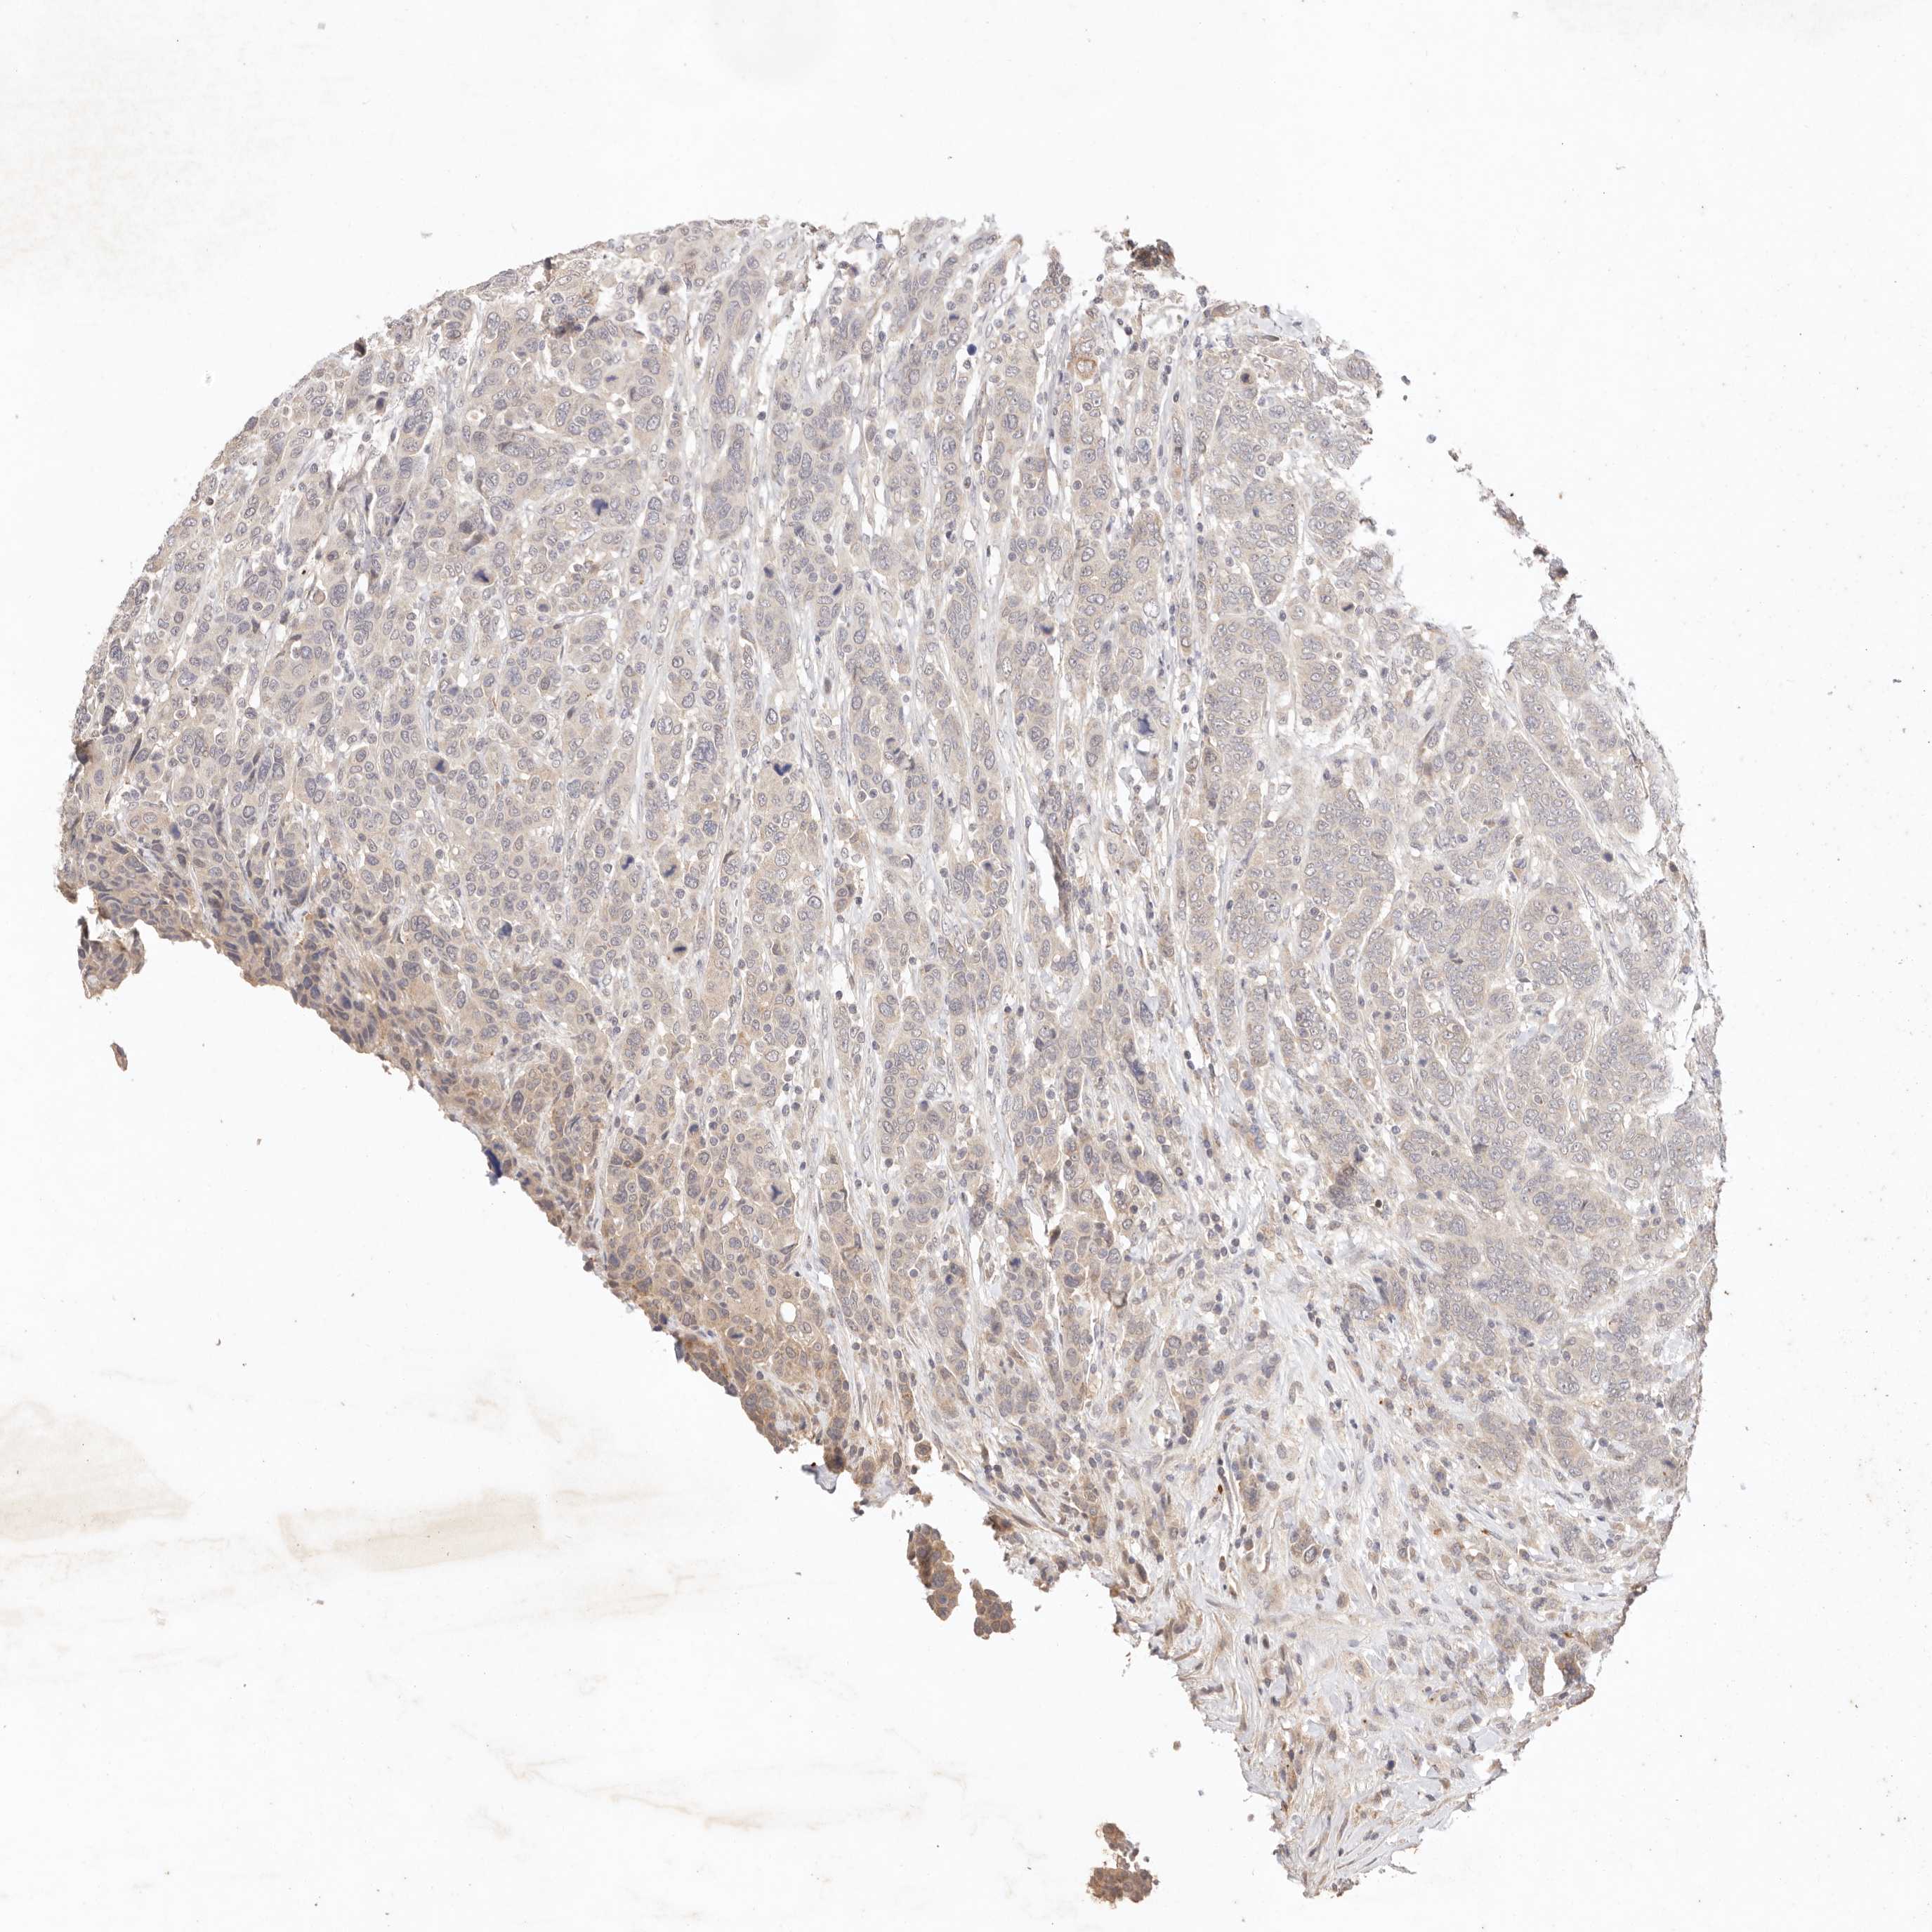

BRCA TCGA BRCA VALIDATION PROTEIN EXPRESSION